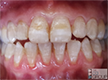

- likewise the opacity surface is initially intact, but this may not last for long as pictured here for a severely Hypomin 6-year molar undergoing "eruptive breakdown" while it's still erupting

- demarcated opacities are usually located in the cuspal half of the

crown and, where multiple opacities appear on a single tooth, they

may vary in colour, size and shape - Hypomin Molars may also elicit a painful response to mild stimuli